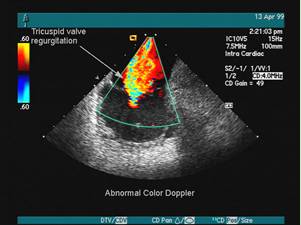

NO.2【彩超】

彩超并非是字面意义上的"彩色的B超",而是在普通B超的基础上出现了彩色-多普勒超声波探测诊断技术,会用彩色标注心脏、血流等指标,彩超观测到的图像以红蓝两色为主。

这种技术能够观测到胎儿的血液流动情况,有利于及时发现胎儿的异常。例如:胎儿颈部如有血流环,则意味着发生了可导致窒息死亡的脐带绕颈。